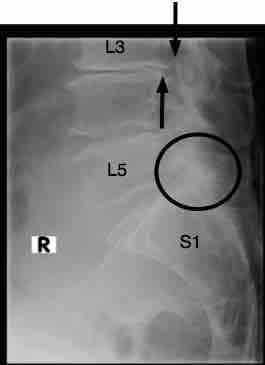

Have you had an xray taken? Degenerative change such as seen in this radiograph may be present.